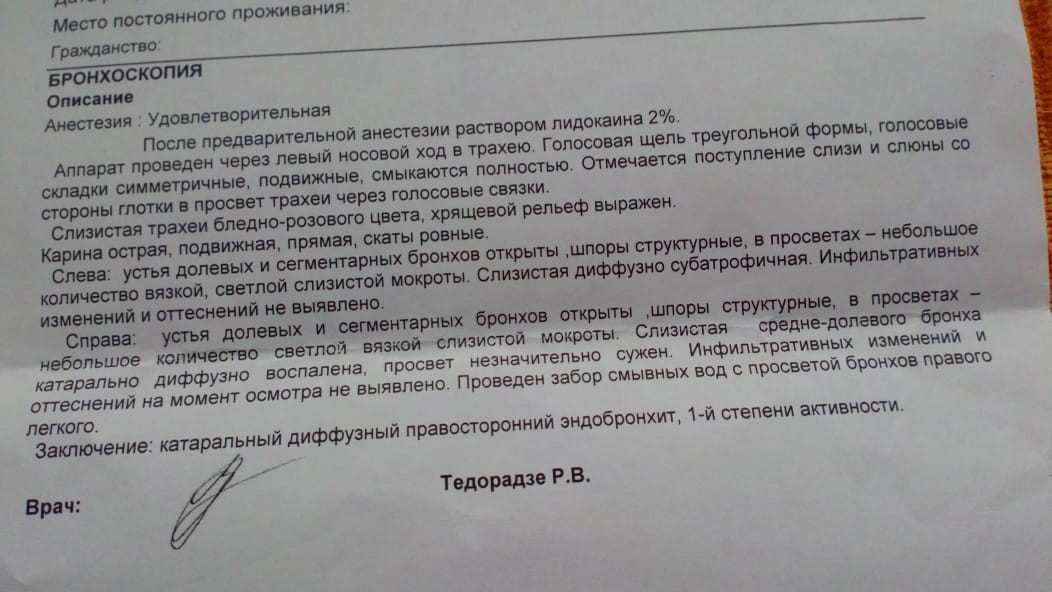

Фотографии и информация о бронхоскопии при туберкулезе